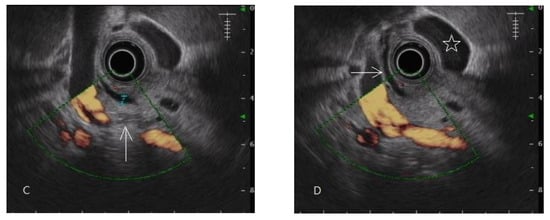

In this study, the diagnosis of pancreatic fibrosis was pancreatic ARFI value > 1.4 m/s (mean of 10 measurements in pancreatic head or body) [16] or meeting the EUS diagnostic criteria of early chronic pancreatitis. EUS-diagnosed early chronic pancreatitis has at least three of the seven total factors of the EUS criteria for early chronic pancreatitis proposed by the Japan Pancreas Society (JPS). The seven factors are lobularity with honeycombing, lobularity without honeycombing, hyperechoic foci without shadowing, stranding, cysts, dilated side branches, and hyperechoic main pancreatic duct margin [35], illustrated by normal and abnormal images in Figure 1 and Figure 2, respectively.

Figure 2.

Endoscopic ultrasonography of early chronic pancreatitis. (A,B) Pancreatic head lobularity (arrow mark) showing heterogeneous parenchyma with hyper/hypo echoic areas mixing, irregular hyperechoic stranding. (C) A hyperechoic focus without an acoustic shadow (arrow mark) in the pancreatic tail. (D) Hyperechoic stranding in body, neck (arrow mark).

In this study on the dyspeptic population, early chronic pancreatitis was defined as pathologically equivalent to pancreatic fibrosis. Pancreatic fibrosis is a term for image diagnosis conventionally used in shear wave elastography, computed tomography, and magnetic resonance imaging [17,38]. Early chronic pancreatitis is a diagnostic term for the EUS procedure first introduced in the nomenclature by a review article published in 1995 [39]. A prospective study using EUS to diagnose alcoholic early chronic pancreatitis was published in 2002 [13]. In the past two decades, early chronic pancreatitis has mostly been diagnosed by EUS in studies [14,15,21,40,41,42,43,44,45]. By definition, early chronic pancreatitis is a syndrome requiring symptoms, risk factors, biomarkers, and image diagnosis, according to an international consensus [19]. The EUS criteria for diagnosing early chronic pancreatitis or chronic pancreatitis were proven to be histologically related to pancreatic fibrosis with approximately 80% accuracy [46,47]. The fibrotic change in the pancreas was focal occurrence [46]. It was evidenced in the distribution of the EUS diagnostic criteria for early chronic pancreatitis, as shown in Figure 2. There was also evidence of focal fibrosis in the pancreatic ARFI procedure, as shown in Figure 5.